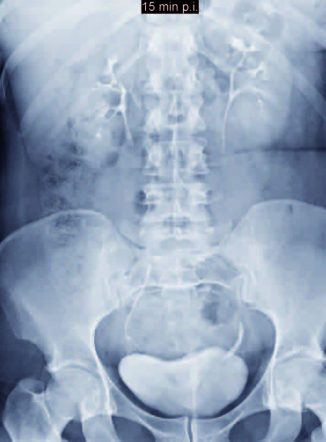

Lungenmetastasen (links im Bild)

In ihrer Behandlung auf Basis der Cellsymbiosistherapie spielen die antientzündliche Ernährungstherapie und die antientzündlichen Pflanzenextrakte (Polyphenole), Omega-3-Fettsäuren, Phospholipide und die – Fettsäure und Phospholipide transportierende vitaminähnliche – Substanz Carnitin eine wichtige, da regulative, die Mitochondrien stabilisierende Rolle. Die Probleme beim Transport und der Versorgung mit Sauerstoff und Nährstoffen, die sich durch die Arteriosklerosis entwickeln, werden dadurch erschwert, dass die Sauerstoff transportierenden roten Blutkörperchen einen Durchmesser von 7 μm haben, das sind sieben Millionstel Meter, wie Sie auf nebenstehendem Bild sehen können.

Unsere kleinsten Blutgefäße, auch Kapillargefäße genannt, haben dagegen nur einen Durchmesser von 3 μm – also 3 Millionstel Meter! Von diesen Kapillargefäßen besitzt der Mensch so viele, dass sie eine Strecke von 100.000 km bilden könnten. Das entspricht einer 2,5-fachen Umrundung unseres Planeten Erde. In der Fachliteratur erscheinen auch Angaben, die von 250.000 Kilometern Länge berichten.